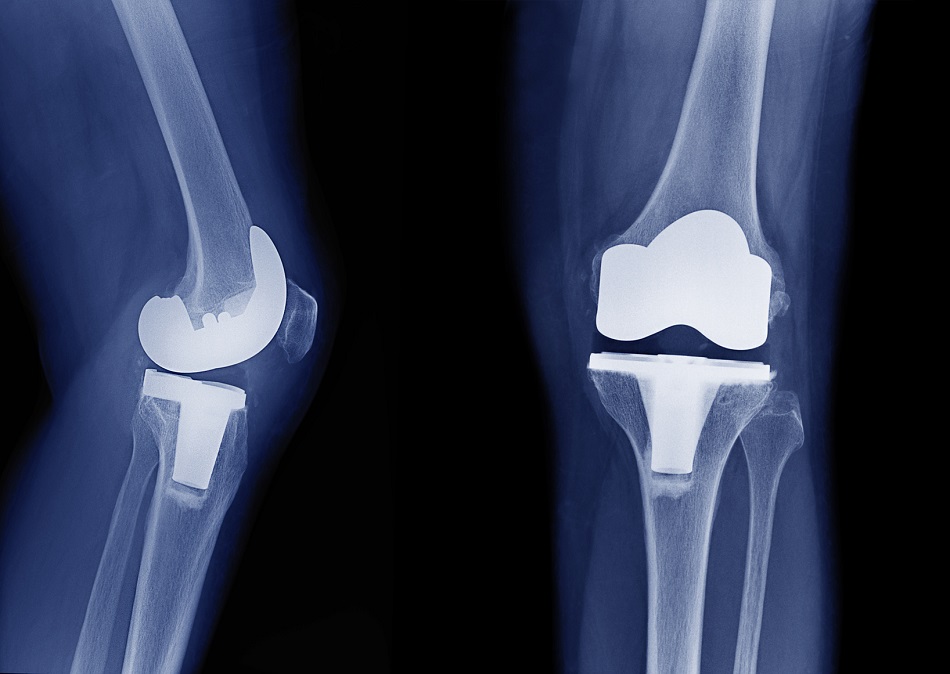

Dexametasona para el manejo del dolor en la artroplastia de rodilla

10 enero 2022

El agregado de dos dosis de dexametasona al tratamiento multimodal del dolor luego de la cirugía de reemplazo de rodilla redujo el dolor y el consumo de morfina durante las primeras 48 horas de posoperatorio. British Medical Journal,  4 de enero de 2022.